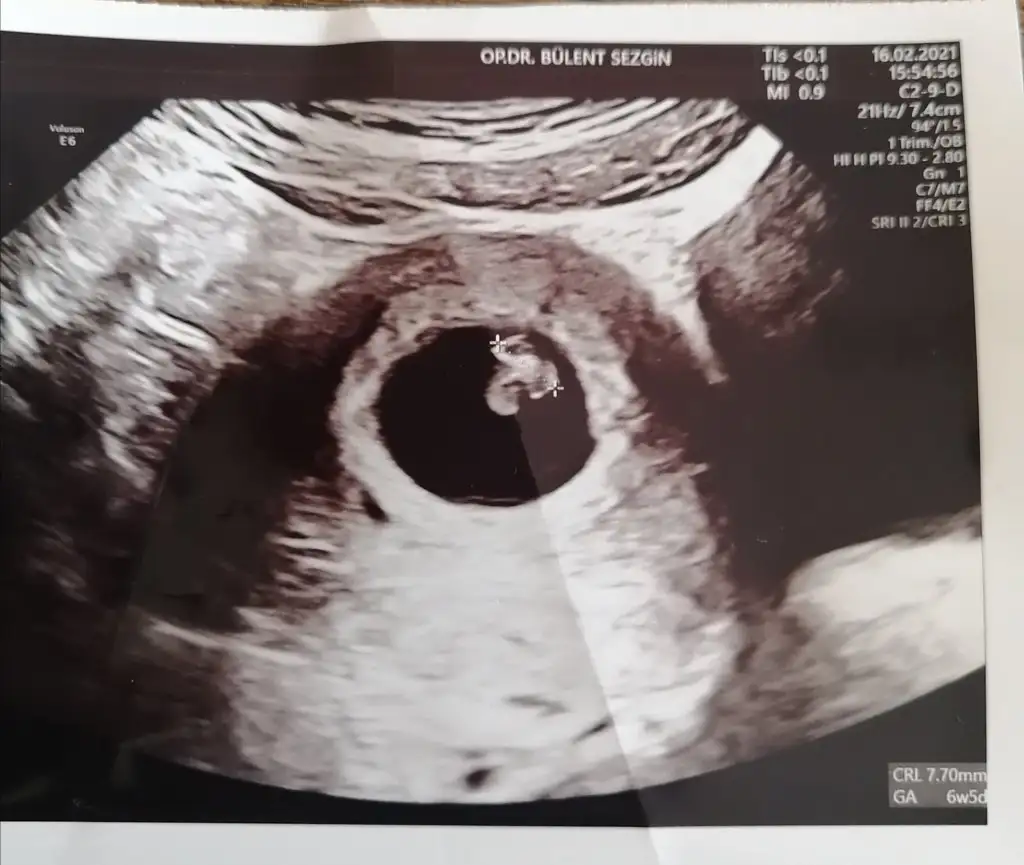

Merhaba arkadaslar ramzi'ye göre cinsiyet tahmini icin yardımcı olabilir misiniz?

Bu arada ultrason goruntusu 6+2,Alttan.

Eklentiler

• 20210217_012905.webp

14,8 KB · Görüntüleme: 161